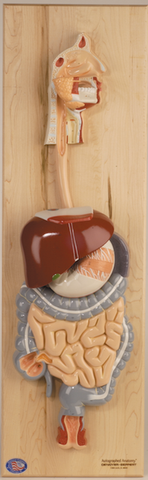

Anatomy

Anatomical models and charts by Body System or Anatomical Region for Nursing, Physical Therapy, and Medical Education.